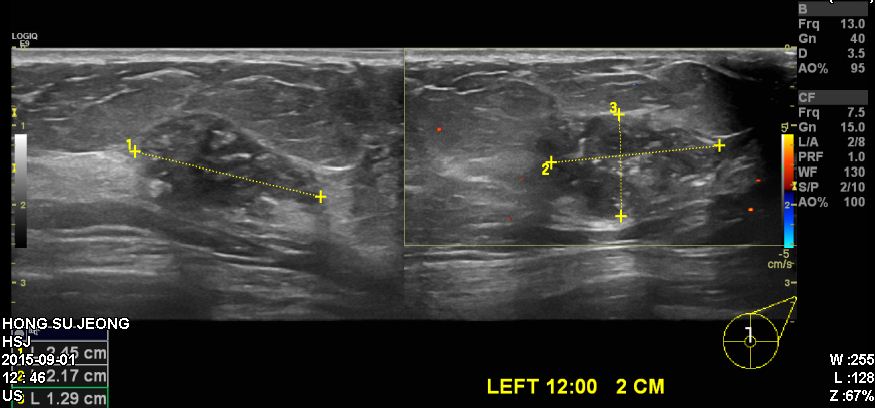

좌측 유방에 만져지는 몽우리로 내원하신 60대 여성분으로 좌측유방에 12시 방향에서

2cm 떨어진 곳에 의심스러운  혹 조직검사 시행 후 좌측 침윤성 유관암 진단 되었습니다.